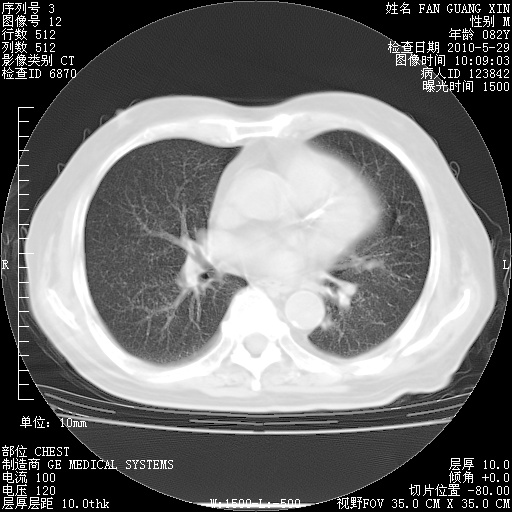

再治疗10天后的肺部CT